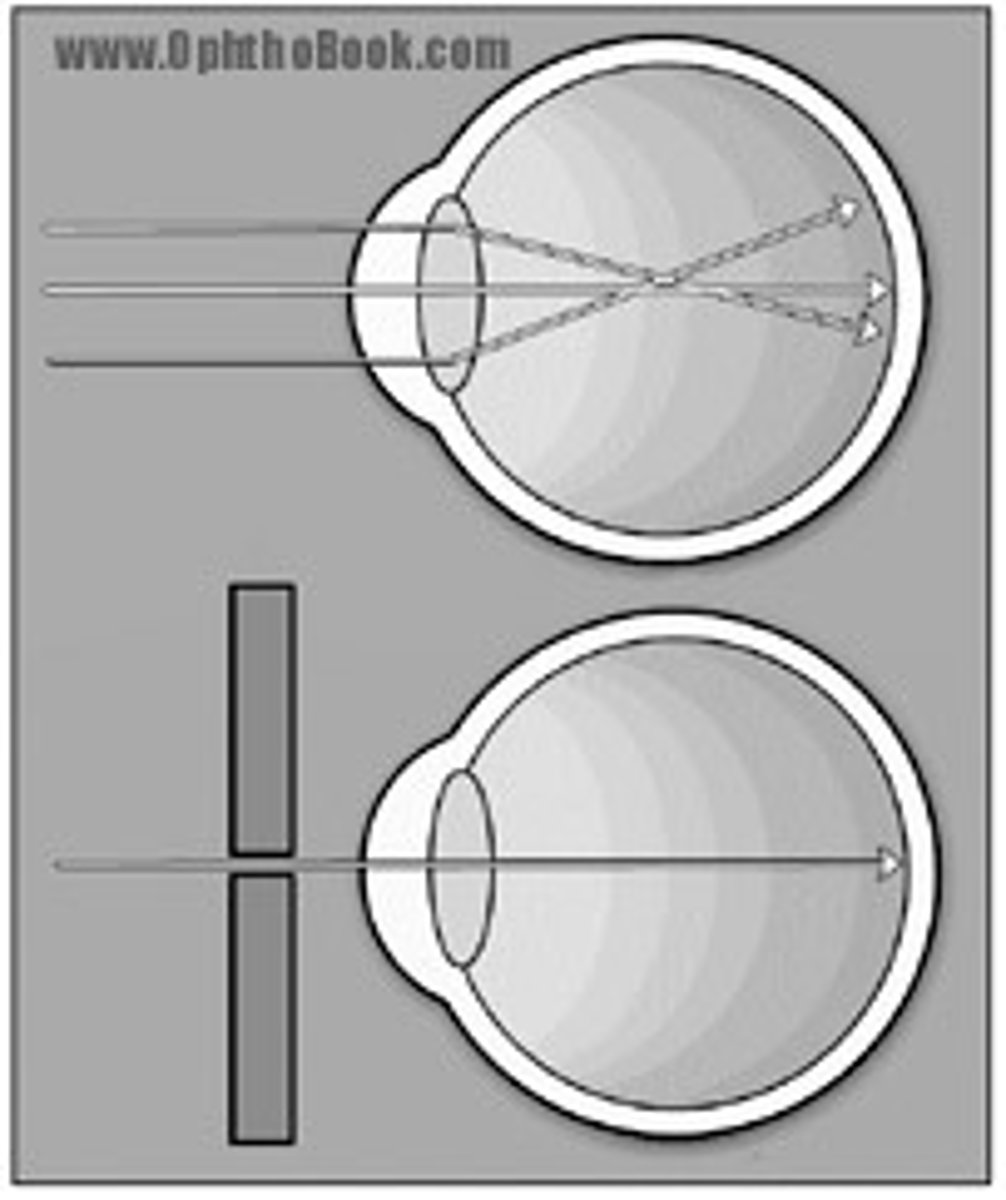

Though there are many exceptions and the patient lens choice should be considered a starting position guide and NOT a rule, in which direction would you most likely rotate the ophthalmoscopic lens selection wheel for a myopic patient (near sighted)?

a) Toward the red (minus) lenses

b) Toward the green (plus) lenses

Though there are many exceptions and the patient lens choice should be considered a starting position guide and NOT a rule, in which direction would you most likely rotate the ophthalmoscopic lens selection wheel for a hyperopic patient (far sighted)?